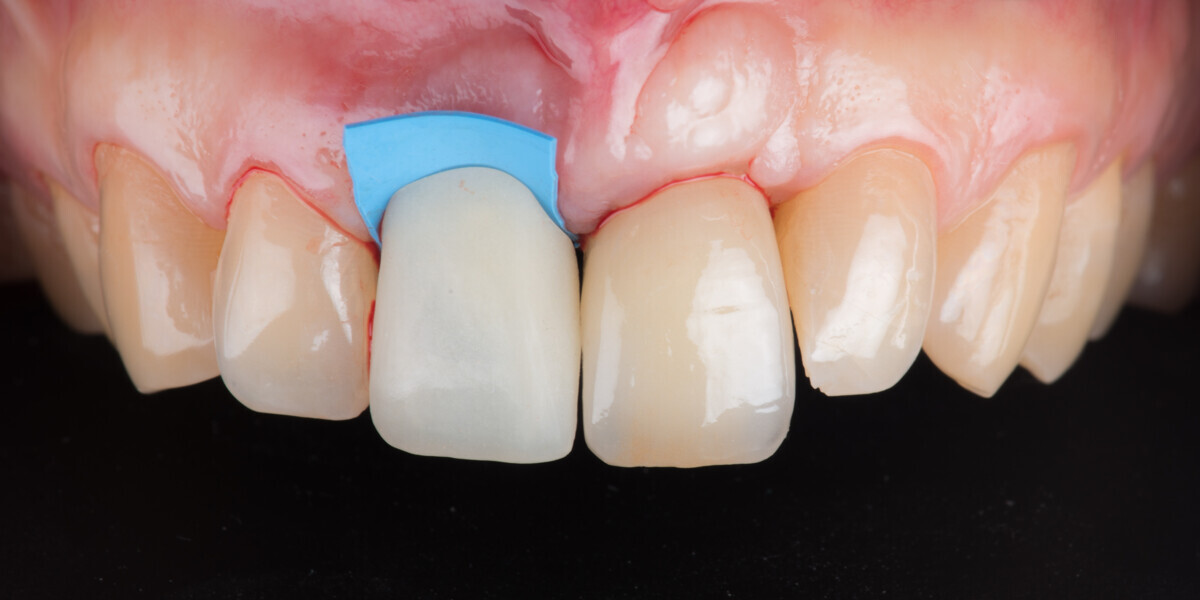

Immediate placement and restoration of a Straumann BLX implant replacing maxillary incisors